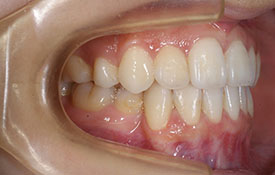

インビザラインの治療例:CASE-1

| プロフィール | 42歳 女性 |

| 所見 | 他院で行われた矯正歯科治療後の後戻りに悩まれて来院されました。 アイライナーの装着は、1日平均20時間ほどでした。 |